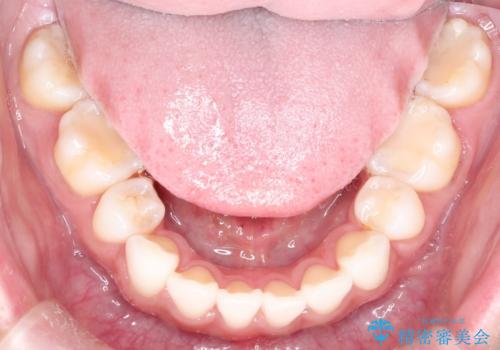

口が閉じにくい 口ゴボの抜歯矯正による改善

- 口が閉じずらく、口元が出ていることを主訴に来院されました。

上下左右の歯を1本ずつ抜歯して、そのスペースを利用して口元を引っ込める計画としました。

口元を下げて口唇を閉じやすくする場合、抜歯矯正をお勧めさせていただくことが多いです。